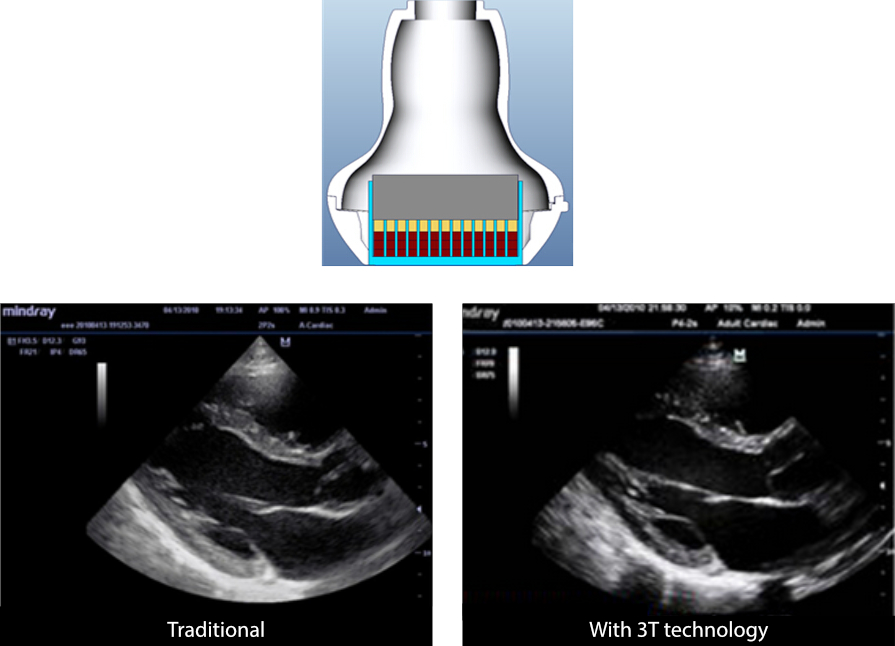

3T Transducer Technology?

Teknologi transduser yang telah dipatenkan Mindray untuk meningkatkan bandwidth gambar dan efisiensi transmisi.

¬Ј Desain tiga lapis pencocokan untuk menghasilkan sensitivitas lebih tinggi, bandwidth lebih lebar, dan meningkatkan S/N

¬Ј Desain pemangkasan total agar derau cross-talk lebih rendah, direktivitas lebih baik, dan resolusi lateral meningkat

¬Ј Desain kontrol termal agar transmisi akustik lebih baik